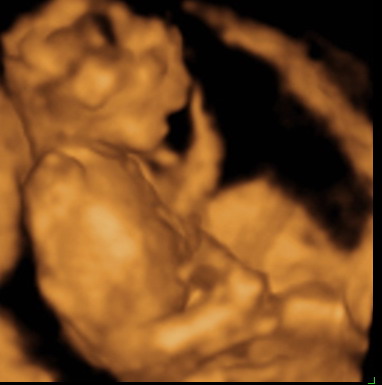

Gratula a kukishoz! Úgy tűnik minden Kisfiúnak ez a szokása! Apa akkor nagyon büszke :lol: :lol: ! Rajta múlt :D ! Kép KUKAC

Kép levitáció Kép Orr+fülfogás

Kép BOX

Kép Lúdtalp nincs :):)lábfej torna Kép Kép Álmos vagyok

Kép guggolás Kép Tipikus pasi-láb között matatás

Kép Nyújtózás

Kép Hello Kép Elég volt, most már alszom